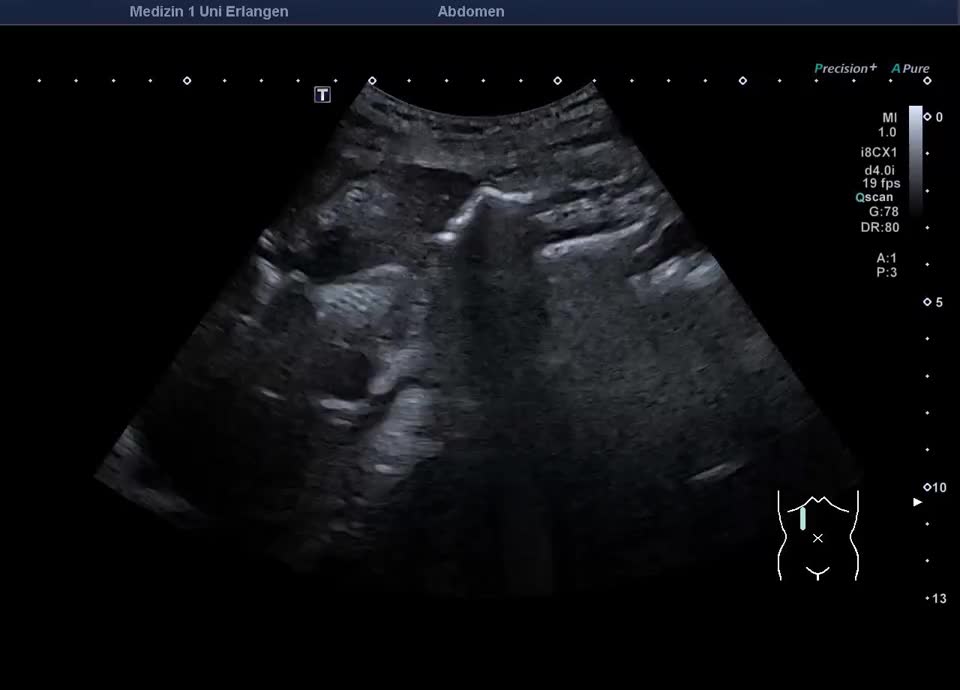

Gedeckt perforiertere Cholezystitis mit konsekutivem Leberabszess und Cholezystolithiasis (Kontrastmittelsonographie im nächsten Bild)